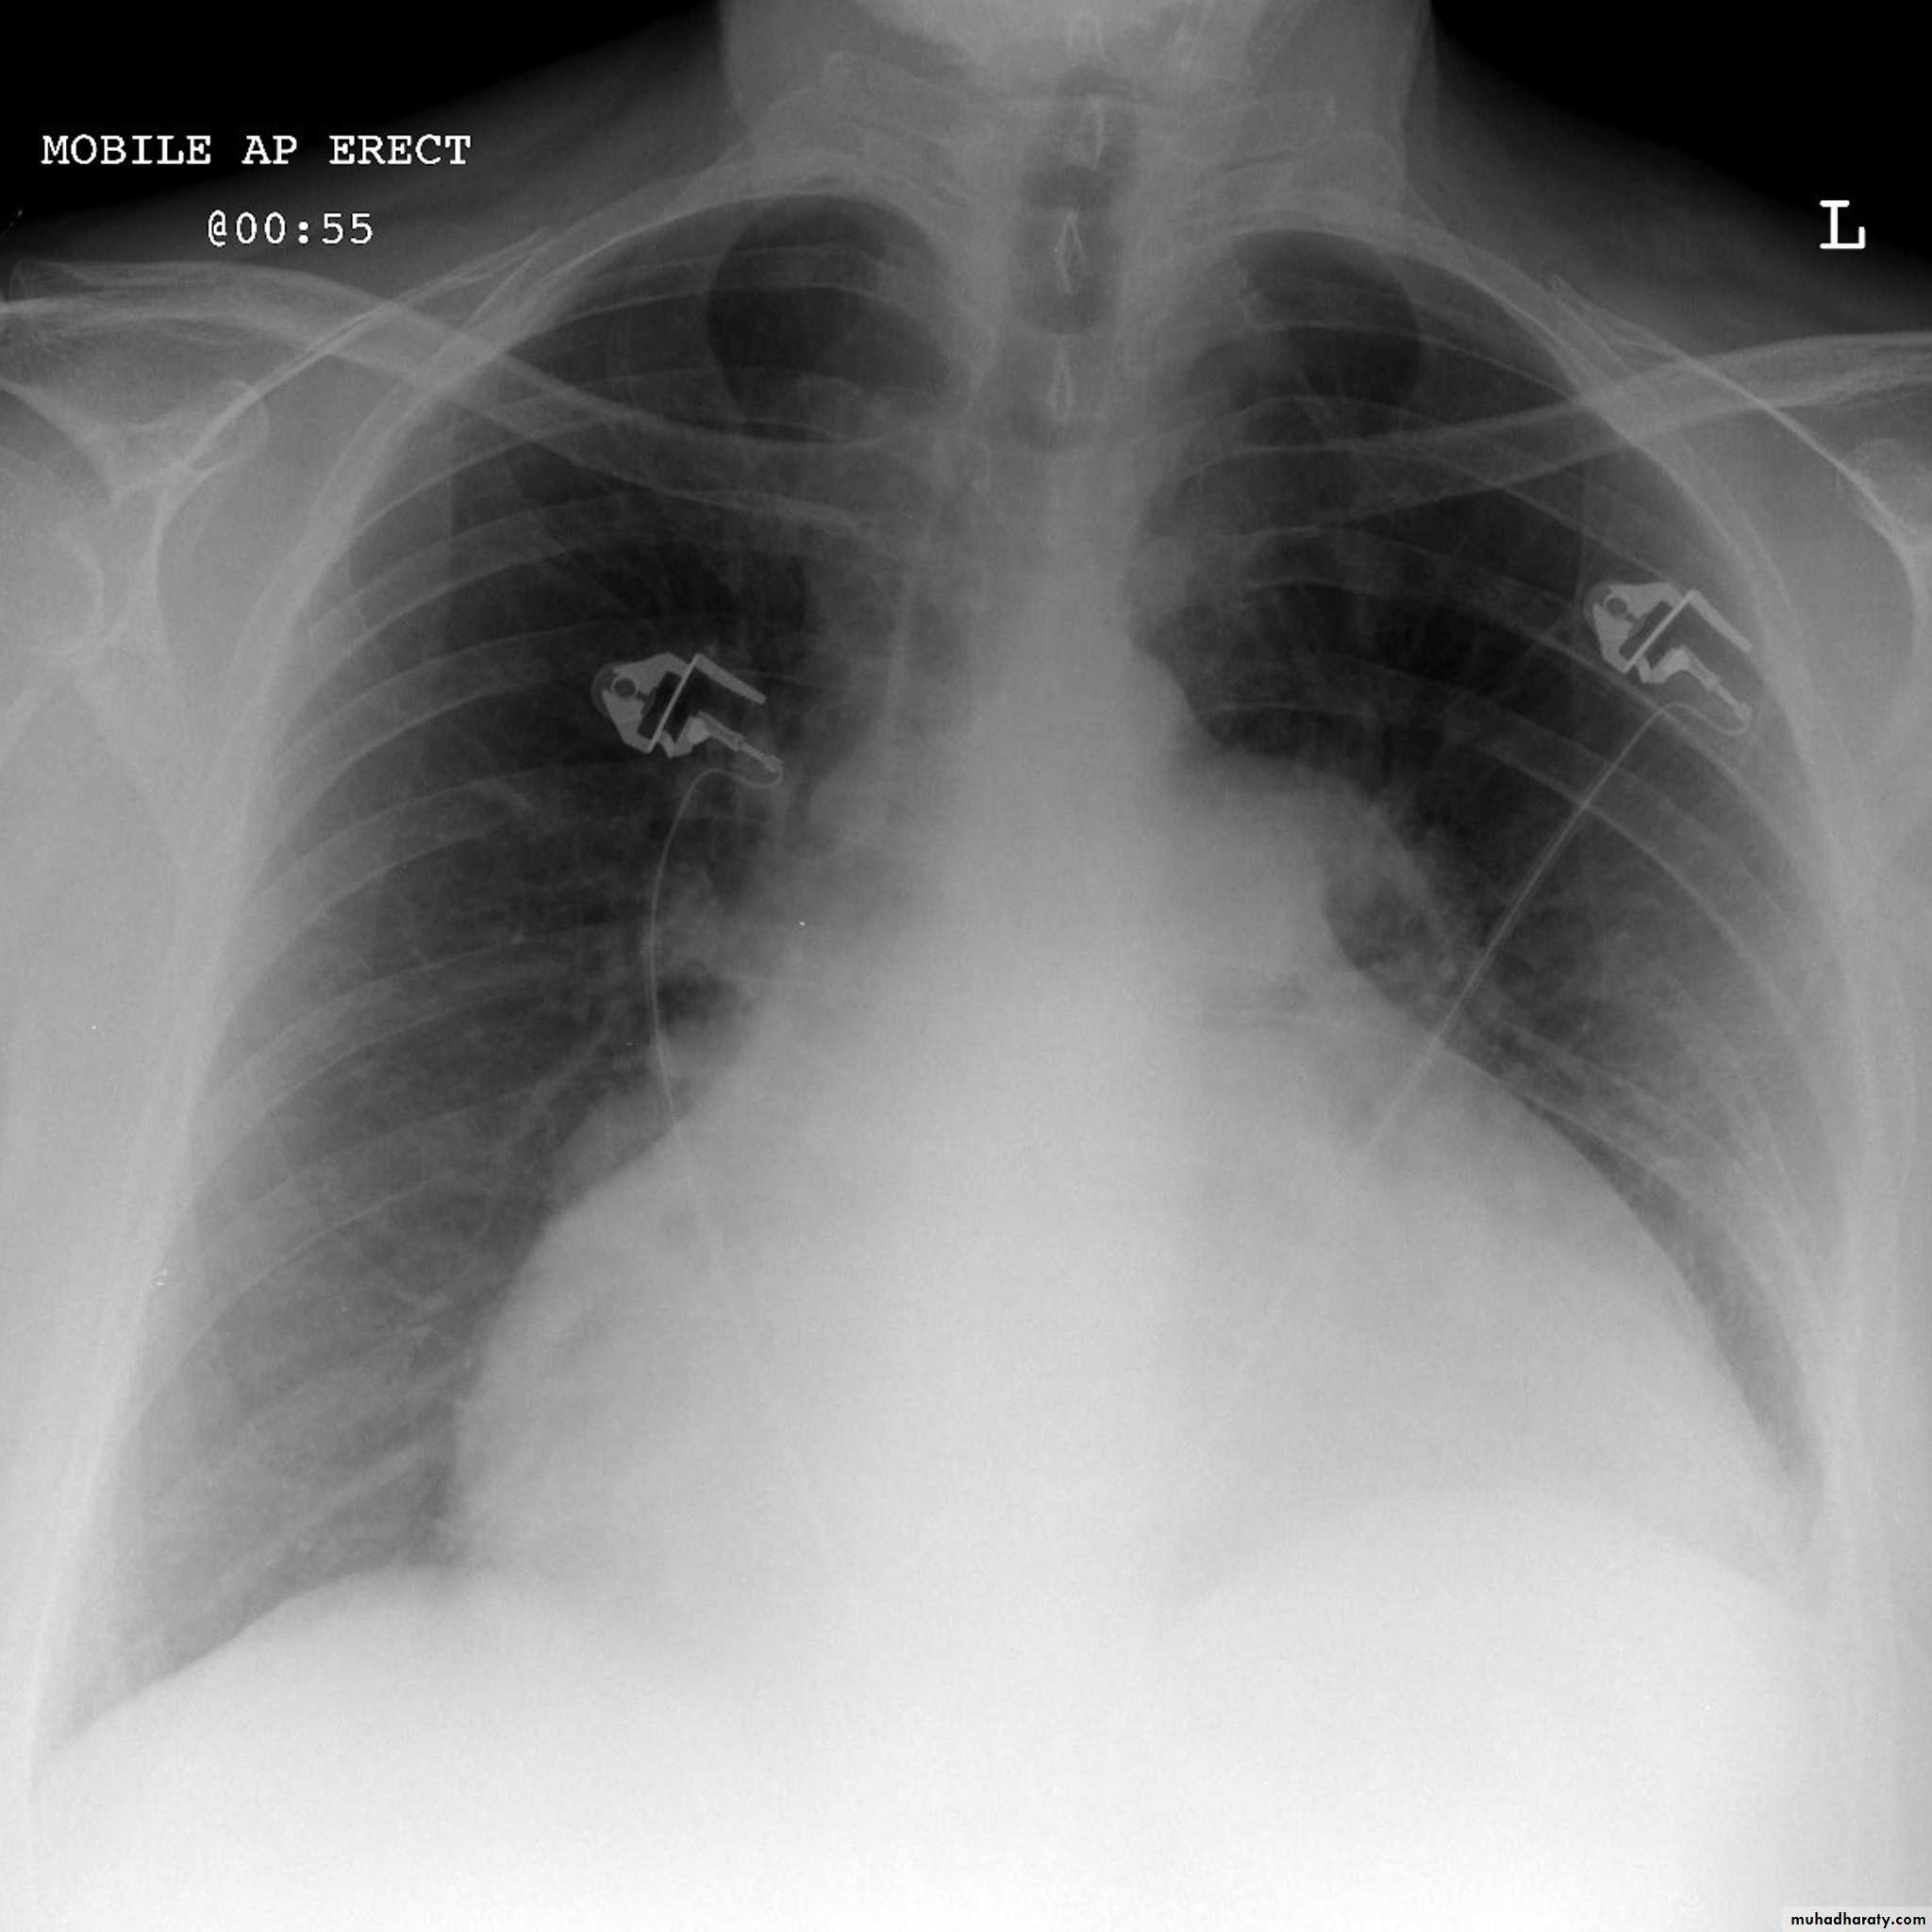

radiograph include if pressure > 25 mmHg the findings of :

1.cardiac size/cardio-thoracic ratio: useful for assessing for an underlying cardiogenic cause or association2.Pulmonary Alveolar edema: bat wing pulmonary opacities

3.Pulmonary interstitial edema: presence of peri-bronchial cuffing///septal lines: Kerley lines become more prominent4.pleural effusions

5.Central pulmonary venous engorgement

6.pulmonary blood flow distribution& upper lobe pulmonary venous diversion

Alveolar pulmonary edema